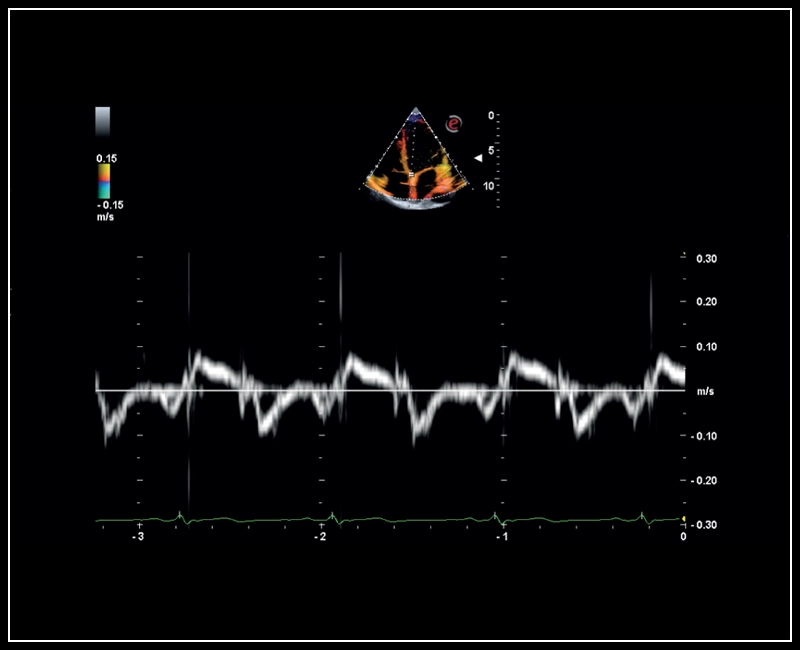

MyLab™Sigma - Mitral valve posterior leaflet analysis with Tissue Velocity Mapping

MyLab™Sigma - Mitral valve posterior leaflet analysis with Tissue Velocity Mapping